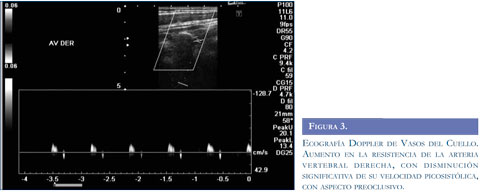

Con los argumentos descritos se realizó estudio de resonancia magnética del cerebro (Figuras 1 y 2) que evidenció infarto isquémico agudo del territorio de la arteria cerebelosa posteroinferior derecha (PICA), ecografía Doppler de vasos del cuello (Figura 3) que muestró aumento de las resistencias de las curvas obtenidas en la arteria vertebral derecha, con disminución significativa de su velocidad picosis-tólica y curvas con aspecto preoclusivo por lo cual se sospechó disección de la arteria vertebral. Se realizó panangiografía cerebral (Figura 4) que concluyó en disección de la arteria vertebral derecha con oclusión distal permitiendo aceptar la hipótesis planteada.